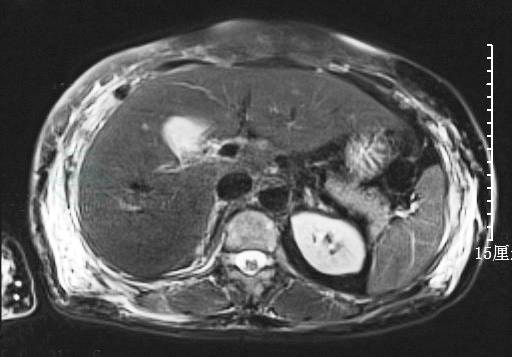

血常规:白细胞计数6.3×109/L,血红蛋白88g/L,血小板计数256×109/L。超敏C反应蛋白12.7mg/L。生化指标:清蛋白34.1g/L,丙氨酸氨基转移酶(ALT)41.2U/L,天冬氨酸氨基转移酶(AST)36.8U/L,肌酐 115μmol/L,乳酸脱氢酶 553U/L,血淀粉酶22 743U/L,尿淀粉酶24 672U/L,血脂肪酶56U/L。全腹部CT示胰体尾稍饱满,胸、腰椎体多发骨质破坏(图1)。

图1 全腹CT

该患者为老年男性,急性起病,以上腹胀痛为主要表现;查体见贫血貌,腹部轻压痛;实验室检查示中度贫血,血、尿淀粉酶水平显著升高;腹部CT提示多发骨质破坏,胰腺稍饱满,但无明显渗出性改变。